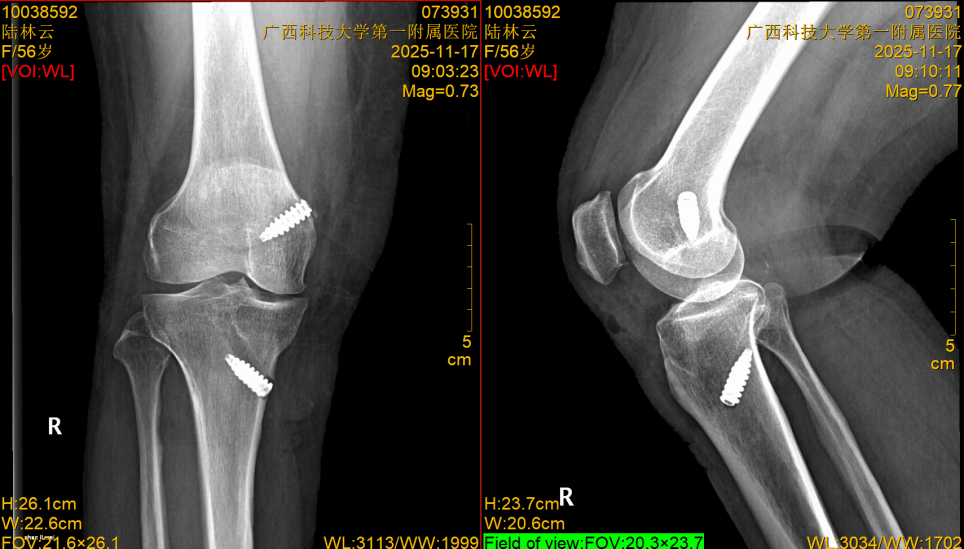

“钥匙孔”里的大工程:四两拨千斤的精准修复,术后复查X线正侧位及抽屉试验,膝关节的稳定性恢复良好。

图6 术后复查X线正侧位